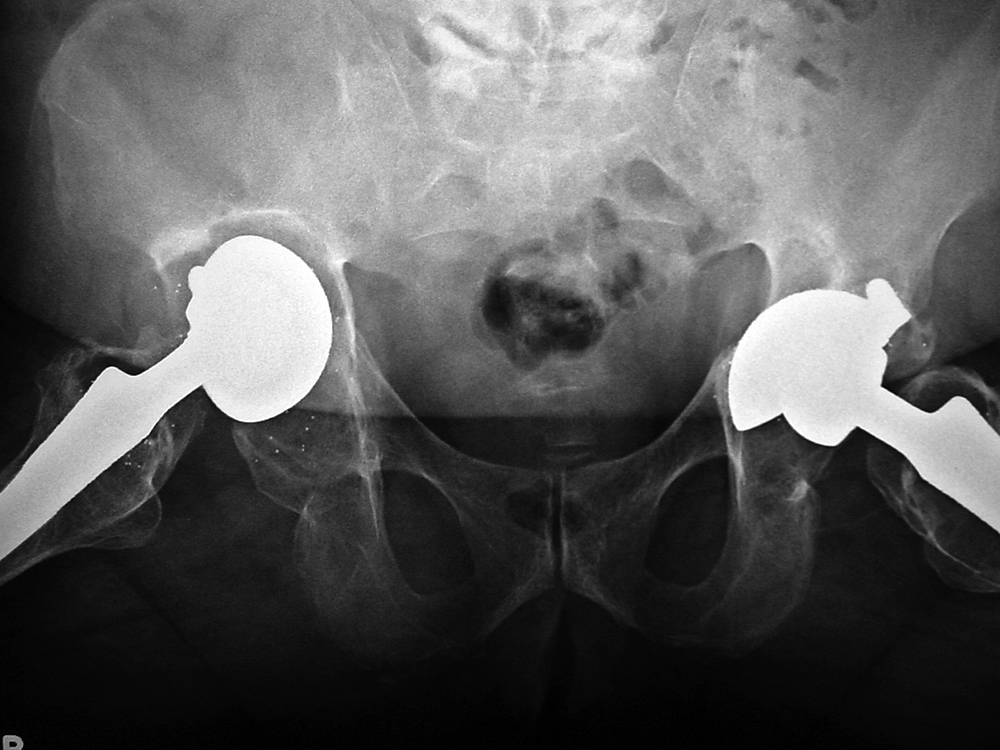

When local particulate matter becomes prominent and threatens or causes prosthesis failure, it is called particle disease or metallosis (figure: particle disease in right hip implant; figure: particle disease left hip CT; figure: left hip polyethylene liner wear; figure: metal-on-metal prosthesis with metallosis). See the discussion of adverse reaction to metal debris in Orthopedic medical devices and cross-sectional imaging: protocols and artifacts - MRI.

Osteolysis and particle disease in right hip implant

There is displacement of the right acetabular implant component and osteolysis from granulomatous particle disease. A left metal upon metal hip implant is present.